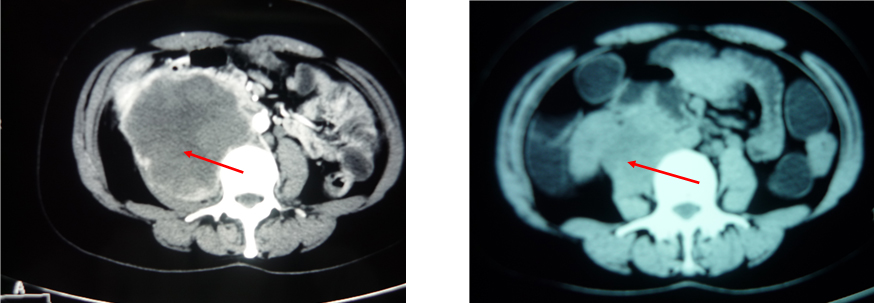

患者李某,女,37岁,广西河池人。患者自诉右下腹部疼痛3个月,曾在南宁某大医院检查诊断为后腹腔恶性肿瘤(肿瘤已侵犯右肾门、输尿管等处),医生下结论说患者无治疗意义。但患者家属不放弃,于2012年10月入住我院肿瘤2区。入院时患者不能站立,用轮椅送进病房,腹痛剧烈,需止痛药镇痛,入院检查磁共振提示:后腹腔肿瘤9×9×12立方厘米(左图)。病理诊断为:平滑肌肉瘤。经过综合评估,专家采用化疗+中药进行了4个疗程的治疗。自第2周期后肿瘤就明显缩小,疼痛消失,生活能够自理,患者一般情况也明显好转。经过3个月的治疗,目前肿瘤已缩小为5×2.5×4立方厘米(右图)。